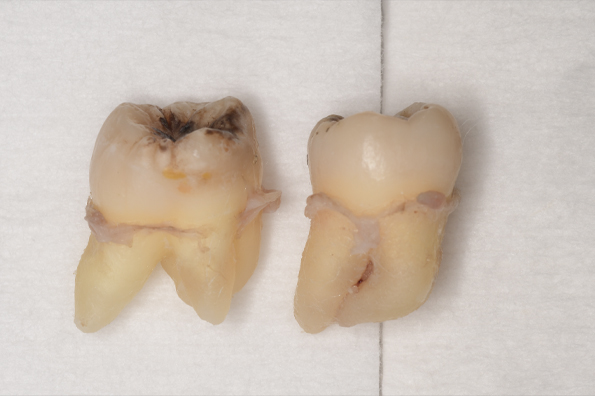

CASE 11

| 年齢・性別 | 33歳・男性 |

| 主訴 | 左上下親知らず抜きたい |

| 抜歯期間 | 30分 |

| 抜歯費用 | 約2,500円(保険内) 別途CT撮影で3,000円 (2022年7月現在) |

| 抜歯内容 | 左上下の親知らず抜歯 |

| 治療方針 |

初めに右下の奥歯が痛いとのことでご来院されました。 右下の親知らずと7番目の歯がカリエスになっていたため、まずは右下の親知らず抜歯と7番目の感染根管治療を行いました。左上下の親知らずもカリエスになっているため、今回抜歯を行いました。 |